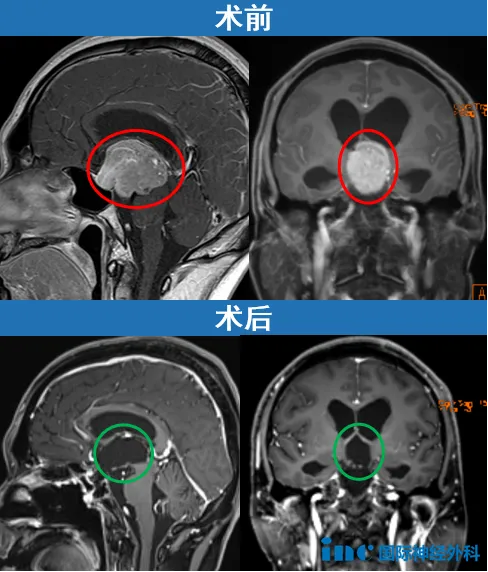

直至1个月后,江先生才真正揪出这一切背后的“凶手”。相关检查发现了江先生颅内的占位性病变,大小约34mm×44mm×38mm,位于蝶鞍及鞍上,并已压迫到第三脑室及中央导水管,导致双侧侧脑室扩张及阻塞性脑积水。

手术当天,福教授按照术前规划顺利取得术中冰冻病理,不考虑生殖细胞瘤、垂体细胞瘤等,因此,在基本确认江先生的肿瘤为需要手术切除的垂体腺瘤后,福教授正式为江先生实施经鼻内镜切除手术。

江先生的手术最终获得十分满意的切除,而且恢复良好,术后正有序地进行激素替代治疗。术后1个多月随访时,江先生术前行走不稳、反应略迟钝、记忆力下降等症状得到明显改善,整体恢复良好,江先生已经可以正常行走,但还稍有些乏力,存在部分记忆混乱等症状。